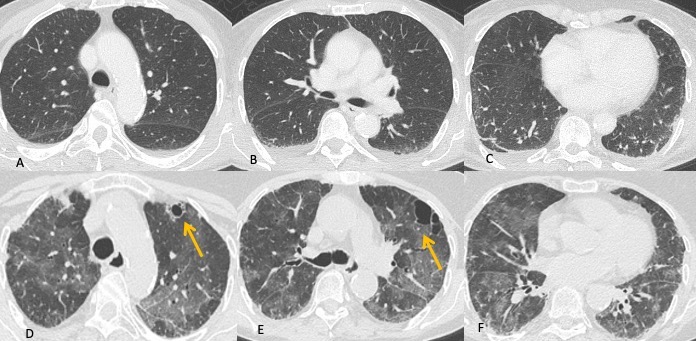

I reperti TCAR sono diversi, in genere nella fase iniziale si documenta la presenza di “vetro smerigliato” diffuso a distribuzione simmetrica che in alcuni casi mostra prevalente distribuzione perilare con risparmio delle zone sub pleuriche e predilezione per i lobi superiori. In seguito, si sovrappongono ispessimento dei setti interlobulari (“crazy paving” pattern), aree di consolidazione parenchimale, noduli e formazione di pseudocisti sub pleuriche (non sempre presenti) che possono andare incontro a rottura provocando pneumotorace spontaneo (Figure 4 e 5).

Figura 4: Donna di 78 anni con diagnosi di Linfoma di Hodgkin. Le immagini assiali (A-B-C) mostrano il parenchima polmonare normale. Un anno dopo la paziente giunge al Pronto Soccorso per un rapido peggioramento della funzionalità respiratoria, dispnea e tosse. La TCAR eseguita alcuni giorni dopo il ricovero nel reparto di Malattie Infettive (D-E-F) mostra la presenza in entrambi i polmoni di "vetro smerigliato" diffuso con relativo risparmio delle zone sub-pleuriche e la comparsa di formazioni pseudocistiche nel lobo superiore sinistro (frecce in D ed E). L’ipotesi formulata e poi confermata dal laboratorio è stata quella di polmonite da Pneumocystis Jirovecii.

Figura 5: Uomo di 68 anni immunocompromesso giunge al Pronto Soccorso per IRA. La TCAR eseguita all’ingresso (immagini assiali A-B-C e la ricostruzione MPR sul piano coronale D) mostrano "vetro smerigliato" diffuso e simmetrico in entrambi i polmoni con relativo risparmio delle aree sub-pleuriche solo in alcune zone nel polmone. L’ipotesi diagnostica formulata è stata quella di polmonite interstiziale. Le indagini di laboratorio hanno in seguito rivelato che l’agente patogeno responsabile del quadro flogistico era lo Pneumocystis Jirovecii. La diagnosi differenziale tra le varie cause di iperdensità parenchimale nei pazienti con IRA non è semplice soprattutto quando le alterazioni sono molto estese e diffuse.